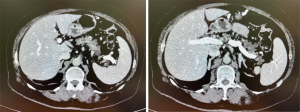

Patient 2, a 60-year-old male, presented with persistent abdominal pain for months, initially managed as chronic pancreatitis. A 36 mm × 43 mm cystic lesion was identified in the pancreatic head via CT and MRI (Figure 3).

Percutaneous biopsy yielded no pathological cells. Subsequent EUS with FNB was performed twice, revealing a hypoechoic lesion measuring 40 mm × 50 mm with hyperechoic walls and solid inclusions, alongside 4 mm dilation of the main pancreatic duct. The first cytological examination of FNB was negative for tumor cells. Due to limited biomaterial, CEA measurements were not conducted initially. Given the inconclusive results from prior tests, DAB was performed, revealing a CEA level of 303 ng/mL and cells with low-grade atypia. This prompted a repeat EUS-FNB procedure, which subsequently detected cells showing high-grade dysplasia consistent with mucinous neoplasia. Despite initial reservations and based on cumulative findings, the decision was made to proceed with pancreaticoduodenal resection. Histological examination confirmed multifocal dysplasia of IPMN of the main pancreatic duct with low and high-grade dysplasia (intestinal type), along with invasive carcinoma, pTis. After 12 months of follow-up, a repeat CT scan showed no signs of progression.